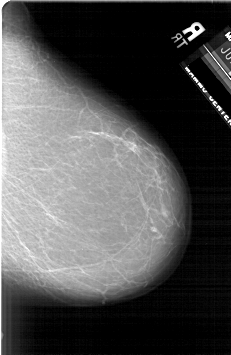

A_1902_1.LEFT_MLO

LEFT_MLO LINES 6226 PIXELS_PER_LINE 3871 BITS_PER_PIXEL 12 RESOLUTION 43.5 OVERLAY